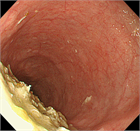

1. アカラシアの内視鏡所見について追加記載を行った。